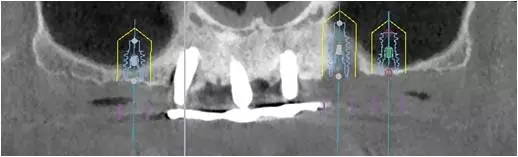

10個月后出現(xiàn)左上頜咬合痛,X線檢查發(fā)現(xiàn)上頜左側(cè)前磨牙區(qū)傾斜種植體周圍低密度影,臨床檢查種植體松動,其余種植體骨結(jié)合良好,遂拔除該種植體(圖3-4)。愈合3個月,CBCT片顯示:25區(qū)種植窩空虛(圖5),愈合不佳,26區(qū)竇底剩余骨高度不足2mm(圖6),其余種植體骨愈合良好,15區(qū)傾斜種植體邊緣骨疑似吸收至第三螺紋(結(jié)合全景片)?;颊咭蠊潭ㄐ迯?fù)。

2、增加上頜種植體數(shù)量,分別與16、25、26植入3顆,行6顆種植體支撐的常規(guī)種植固定義齒修復(fù)(圖7)。16、25、26區(qū)剩余骨高度嚴(yán)重不足是該方案的不利方面,存在因需要上頜竇底提升手術(shù)所帶來的相應(yīng)手術(shù)風(fēng)險。但是,上頜竇底提升術(shù)是一個成熟、可靠的技術(shù)方法,經(jīng)過與患者充分溝通,最終選擇了這一方案。